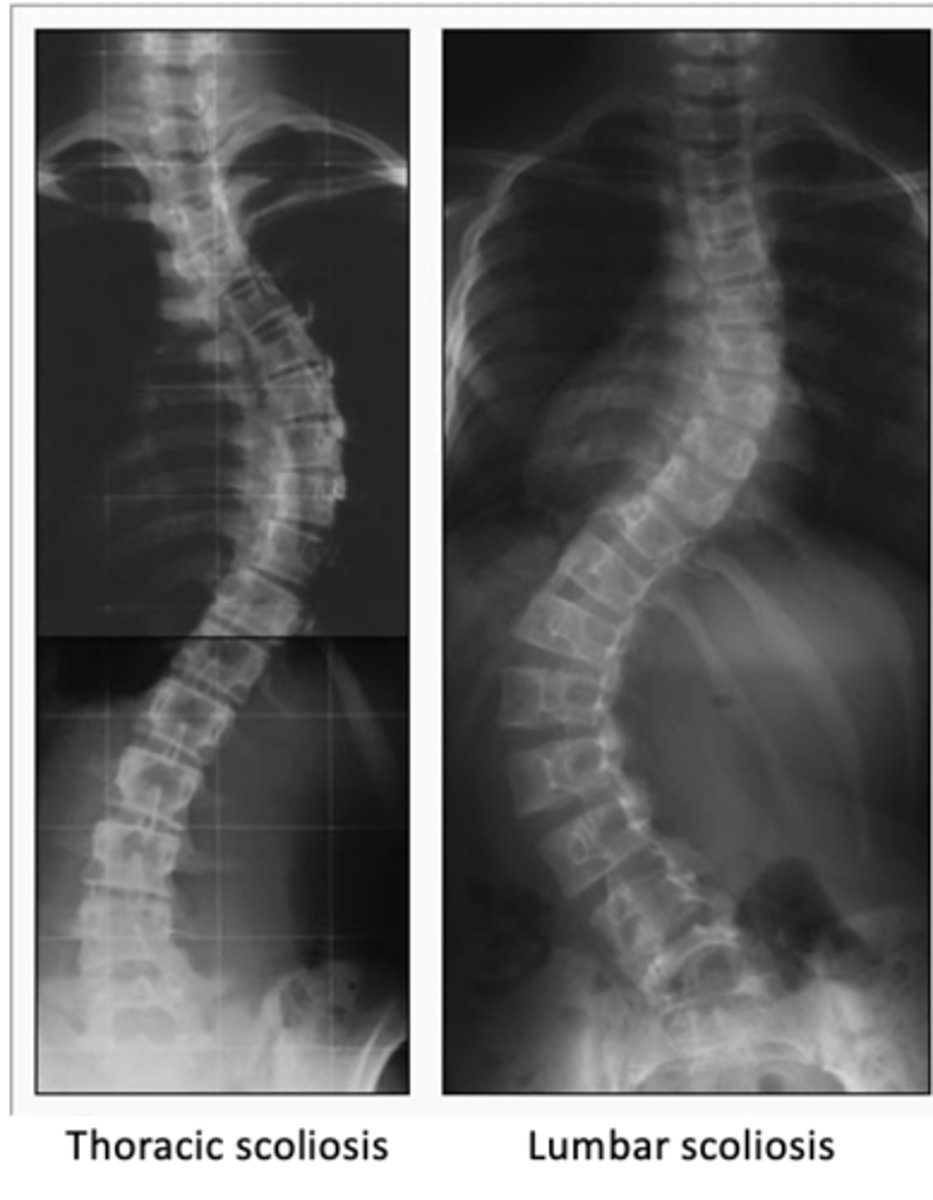

thoracic vs lumbar scoliosis

Cardinal signs of scoliosis

Uneven shoulders or iliac crest

Prominent scapula on convex side of curve

Asymmetry of thoracic cage

Treatments:

- Depend on severity and likelihood to progress

- Curves 20-30°: Considered

- Curves 30-40°: Bracing

- Curves 40-45°+: Surgery